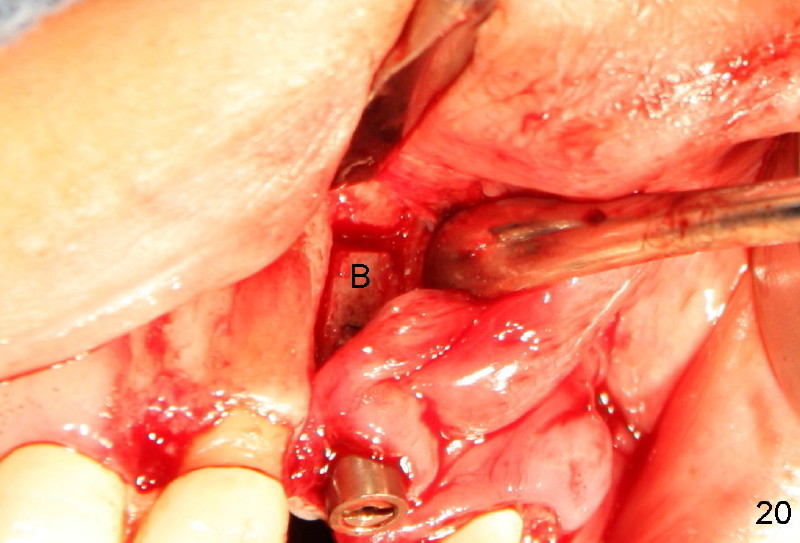

Segmental Osteotomy for Misplaced Implant

This corrective surgery was performed by Dr. Bernee Dunson.

Xin Wei, DDS, PhD, MS 1st edition 12/21/2011, last revision 12/23/2011